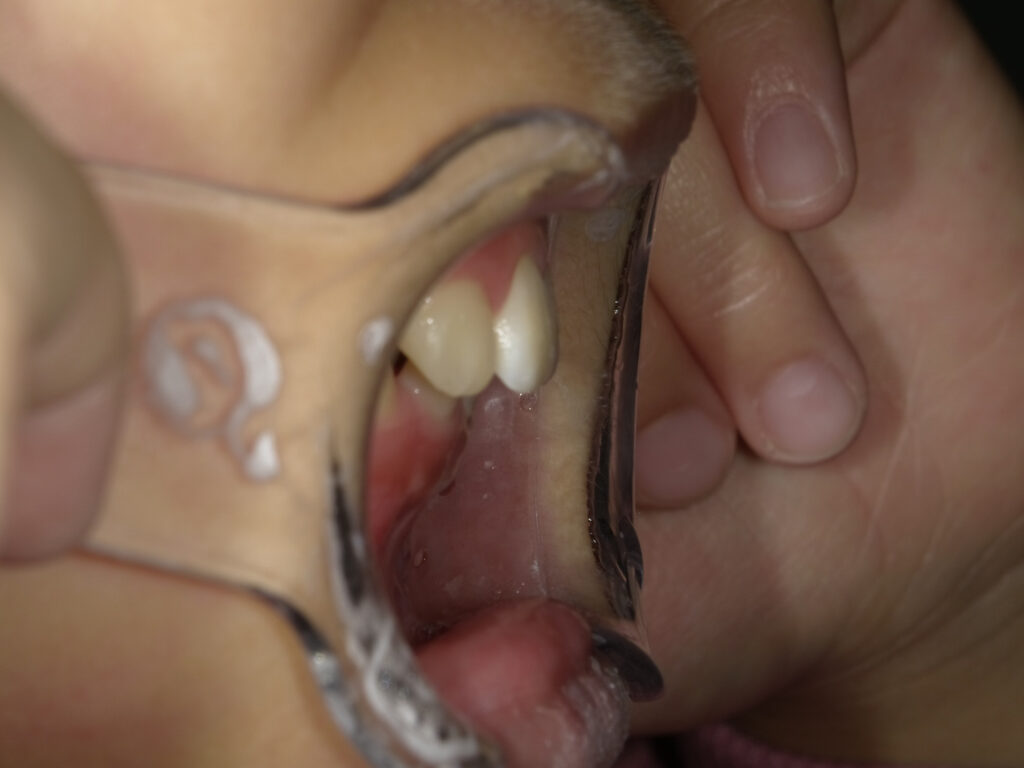

オーバージェット

治療前

治療後

保定中経過(1年後)